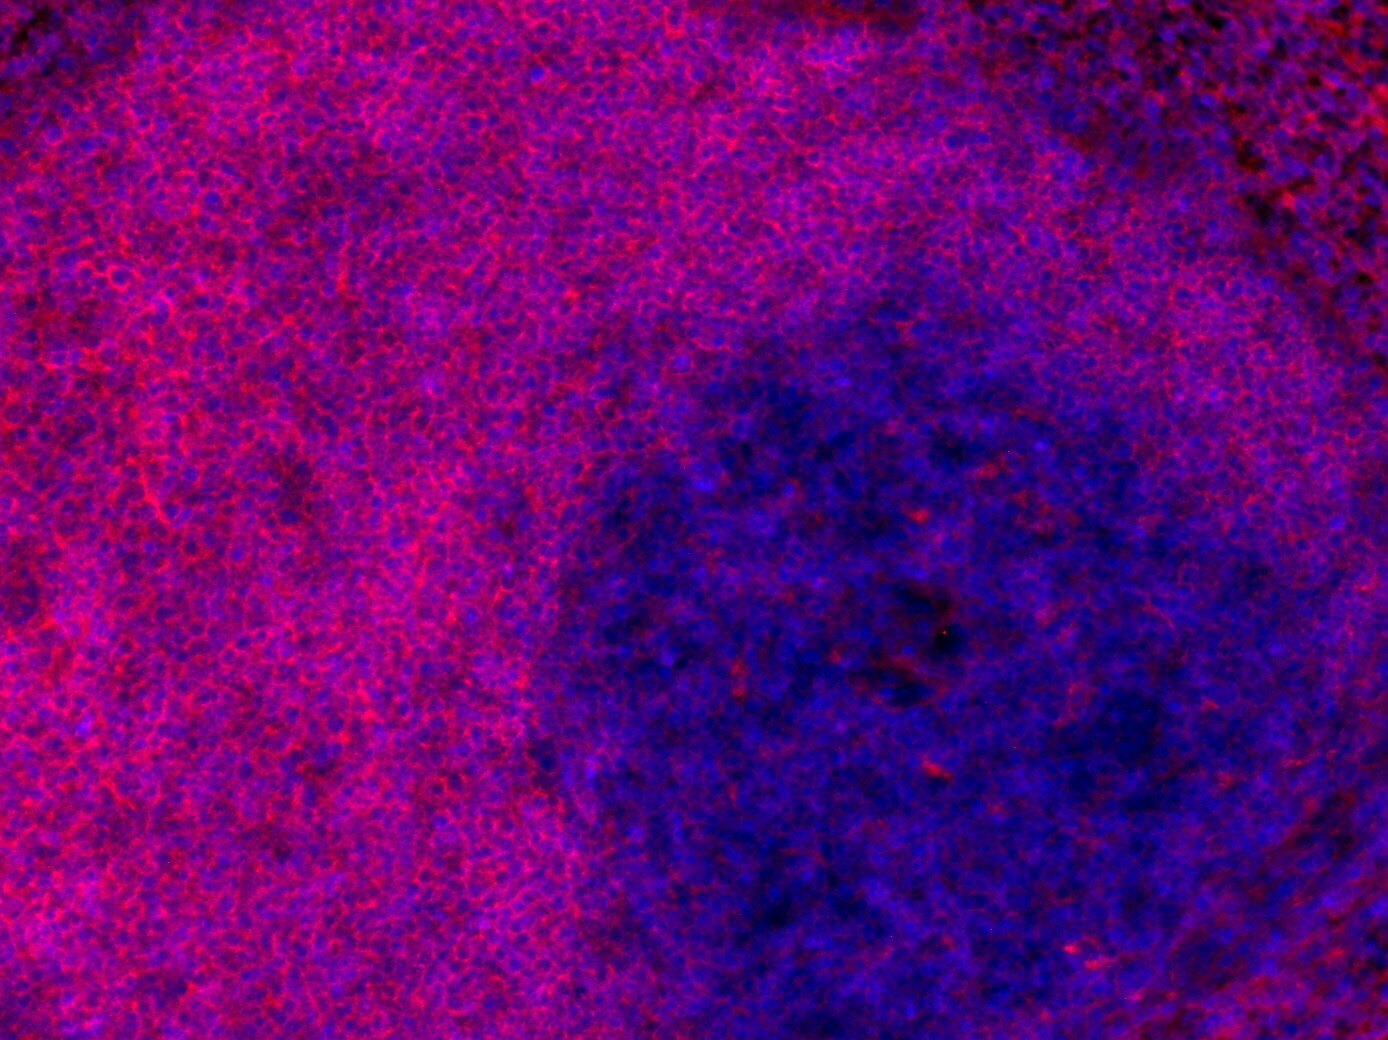

IHC: 1 : 200 gallery

IHC-Fr: 1 : 200 gallery

Immunohistochemistry (IHC) on 4% PFA perfusion fixed tissue with 24h PFA post fixation. Immunoreactivity is usually revealed by fluorescence or a chromogenic substrate. Some antibodies require special fixation methods or antigen retrieval steps. For details, please refer to the ”Remarks” section.